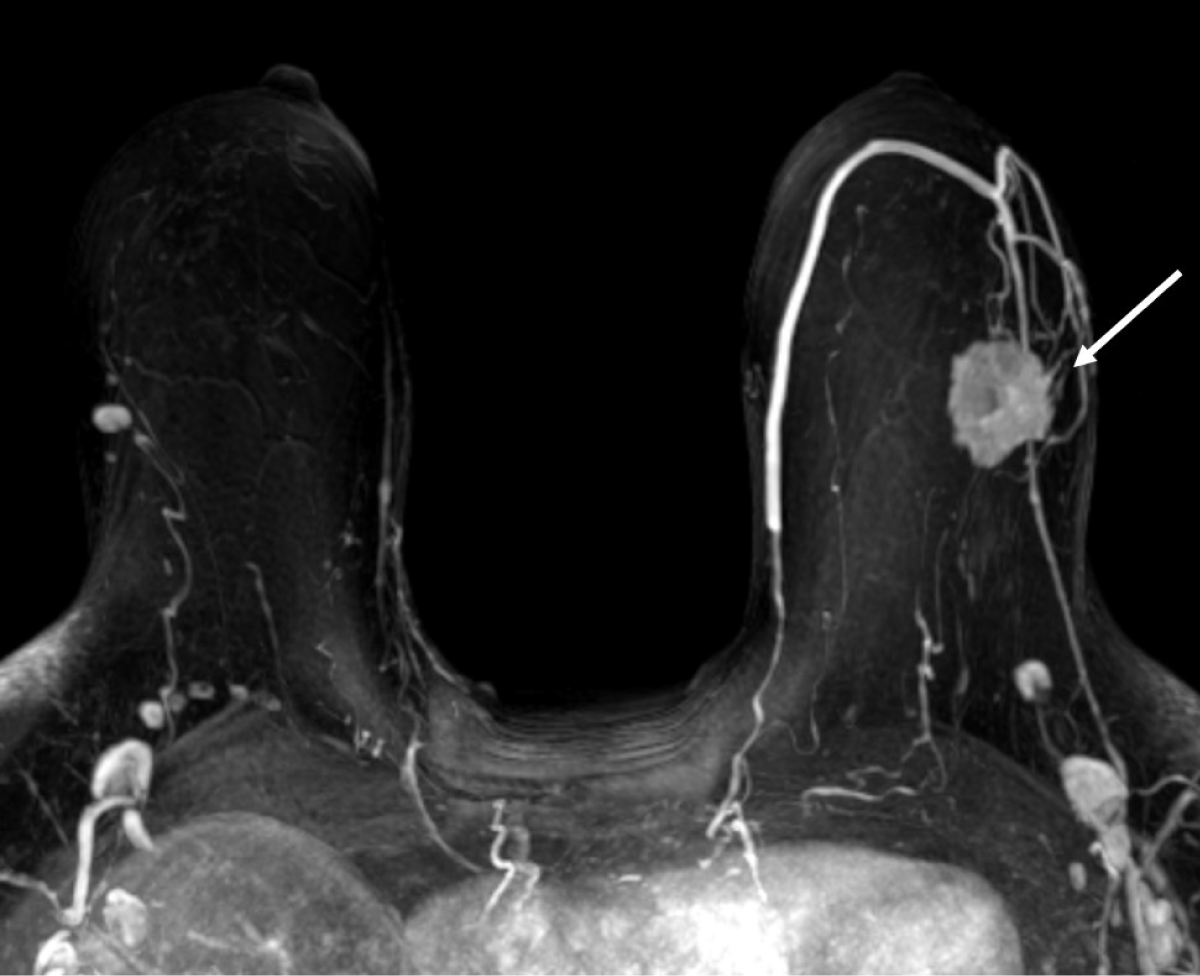

Figure 1: Maximum intensity projection MR image shows a 3 cm irregular enhancing mass in the upper outer quadrant of the left breast (arrow). View Figure 1

A 55-year-old woman presented to our tertiary care facility referred from an outside institution after a 3 cm mass in her left breast was identified (Figure 1). The mass was biopsied, and she was subsequently diagnosed with a high grade invasive ductal carcinoma (IDC) (Figure 2). The cancer was negative for estrogen receptor, progesterone receptor and Her2. Additionally, the proliferative rate as assessed by Ki-67 was 85 percent. An axillary lymph node was suspicious by imaging, but not biopsied. A nuclear medicine bone scan with a Tc-99 m radiotracer was used to stage her cancer (Figure 3). The imaging showed increased radiotracer uptake in the right proximal femur and right distal tibia suggestive of metastases and therefore, the patient was considered to have stage IV metastatic breast carcinoma. However, radiographs of the right femur and tibia showed stable lesions without aggressive cortical involvement and a ground glass appearance suggestive of fibrous dysplasia (Figure 4A and 4B). A subsequent biopsy of the proximal femur lesion showed atypical fibrous tissue with S-shaped woven bone trabeculae that tested negative for MDM2 amplification, essentially ruling out low grade osteosarcoma which can sometimes histologically mimic FD [11] and confirming the imaging impression of fibrous dysplasia (Figure 5). Additional genetic testing showed that the fibrous dysplasia was caused by a somatic mutation on codon 201 of the GNAS gene, substituting cytosine in CGT for thymine (TGT). As the fibrous dysplasia was found incidentally as part of the patient’s metastatic work up and was generally asymptomatic, it was clinically followed. Her triple negative breast cancer responded to preoperative chemotherapy, and a subsequent left breast segmental mastectomy showed only treatment related changes and no residual disease. The sentinel lymph nodes were negative for metastatic carcinoma. The breast specimen was evaluated by molecular sequence analysis which revealed no mutation in exon 8 or 9 of the GNAS gene. The patient is currently well with stable polyostotic fibrous dysplasia and without residual carcinoma.